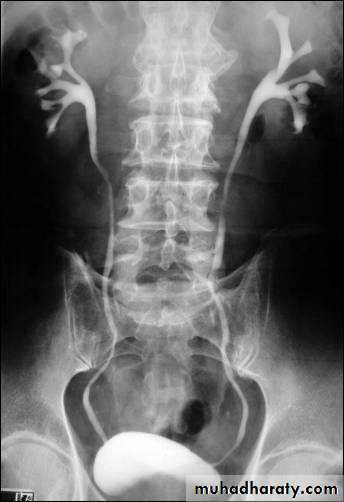

Normal IVU series

Failure of contrast to pass to ureters due to both sided mid ureteric stones

LT sided upper Ureteric stones

Bilateral HU + HN